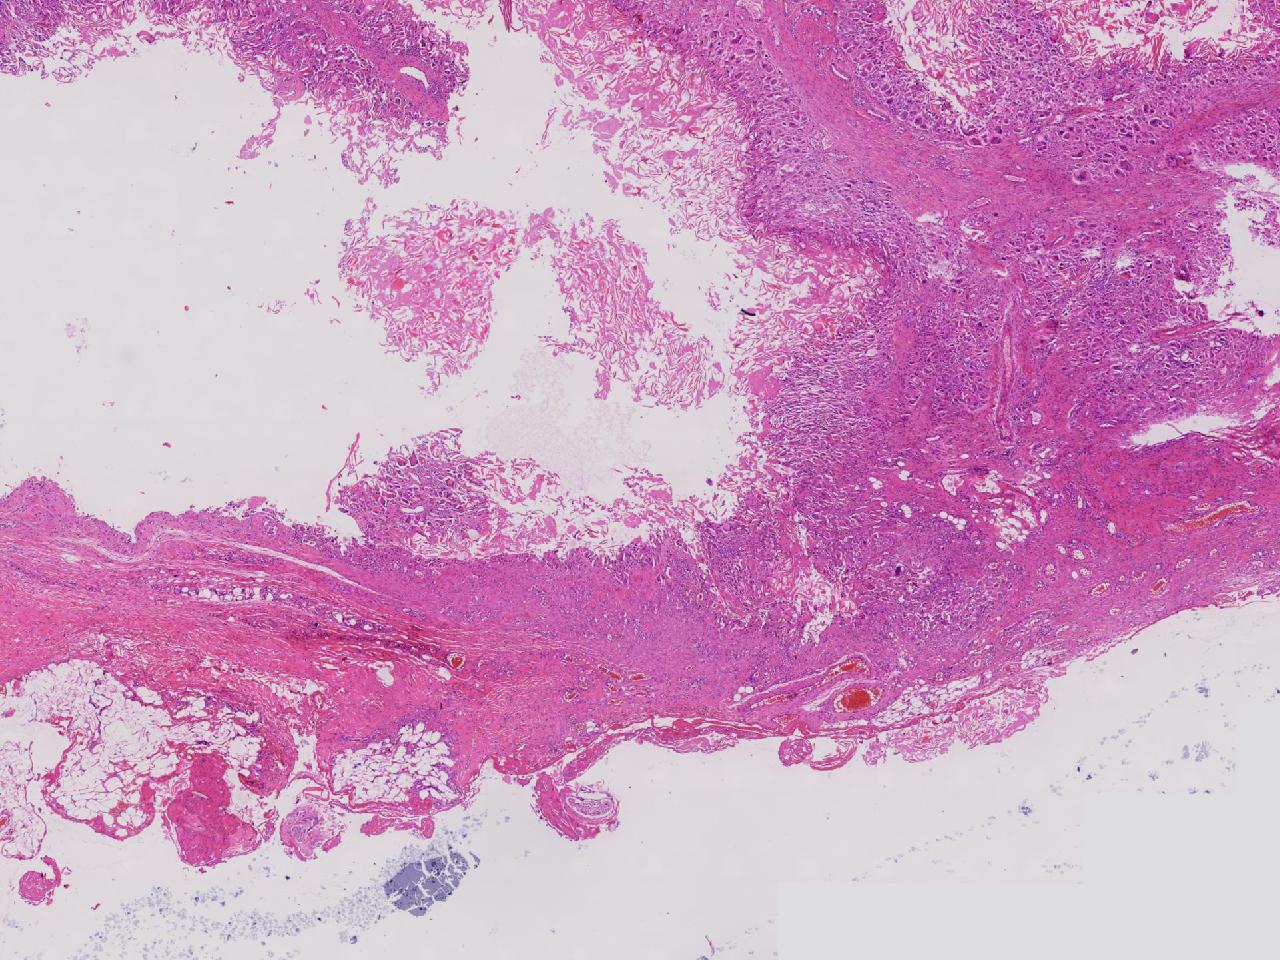

皮样/表皮样囊肿伴周边异物巨细胞反应?

右侧臀部皮下肿物10余年,渐增大,无破溃,无疼痛。

右侧臀部皮下肿物

囊性肿物一个,直径2.5厘米,肿物位于皮下。

异物肉芽肿性炎?

表皮样囊肿伴异物肉芽肿性炎。